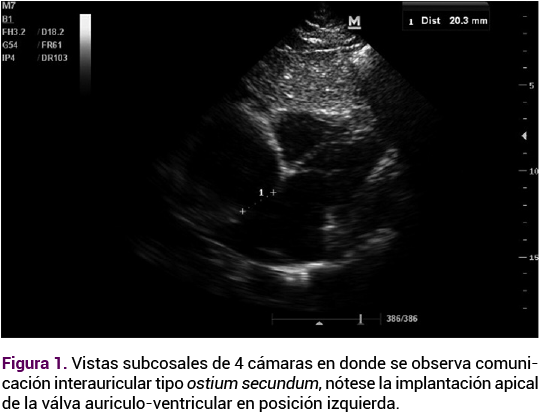

El ecocardiograma transtorácico reportó una comunicación interauricular tipo ostium secundum amplia de 27 mm (Figura 1) y comunicación interventricular subpulmonar de 15 mm (Figura 2), estenosis valvular pulmonar moderada con gradiente de 55 mmHg (Figura 3) ventrículos no dilatados, función sistólica preservada, presión sistólica ventricular ligeramente aumentada del ventrículo sistémico. Por lo anterior, se sugirió hipertensión pulmonar no grave, dextrocardia y situs inversus. Se confirmó el diagnóstico de trasposición congénitamente corregida de las grandes arterias.

Figura 2. Imagen ecocardiográfica compatible con comunicación interventricular subpulmonar, apreciable en ventana de evaluación estructural.